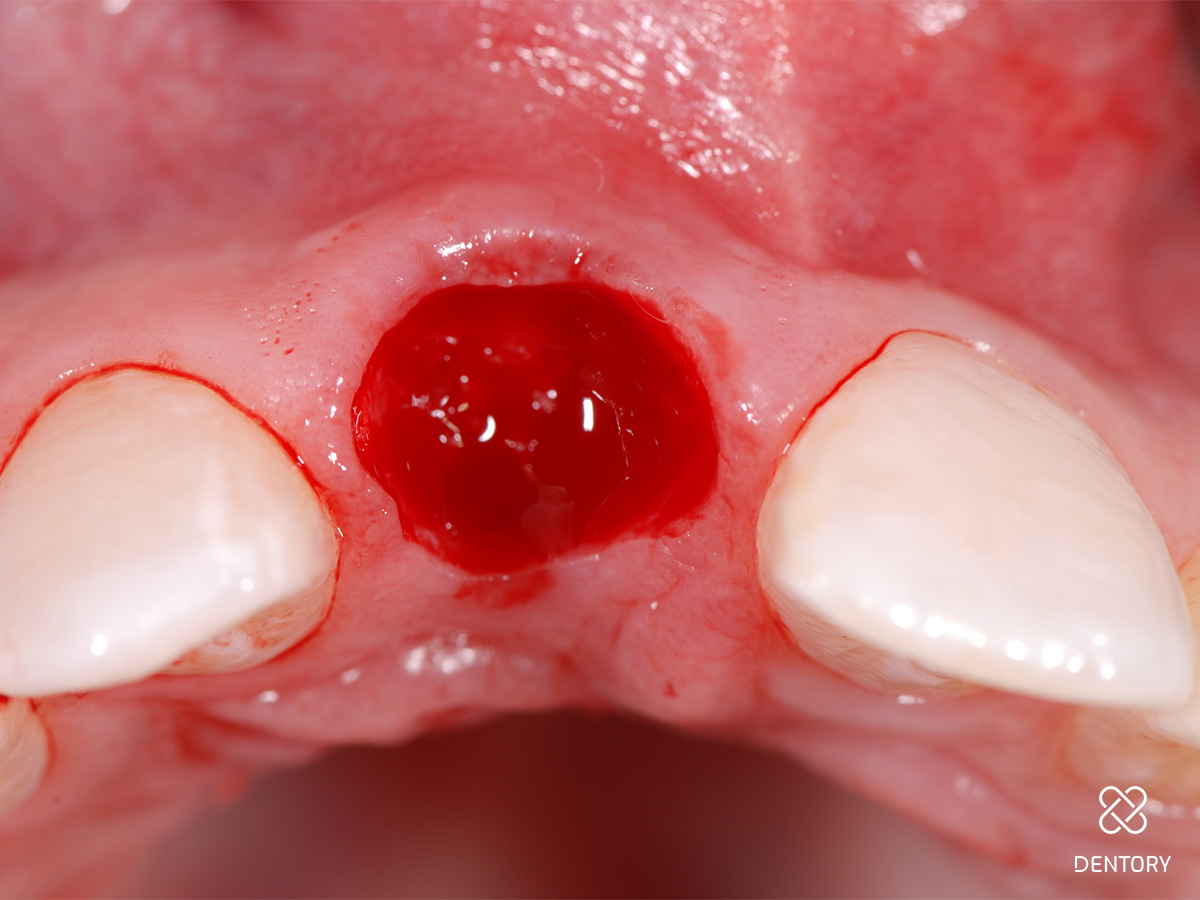

Abbildung 1

Ausgangssituation: Nicht erhaltungswürdiger Zahn 11 aufgrund einer externen Resorption.